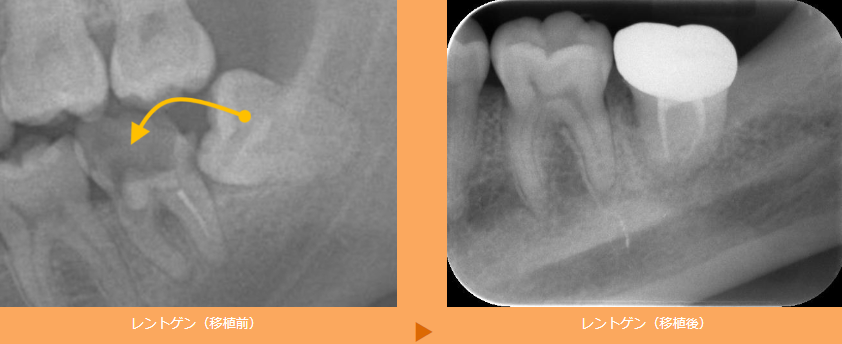

歯の移植:失った歯を、自分の歯で補う治療です

歯を失った場合、何らかの方法で歯を補うことが必要です。もっとも知られている方法には、入れ歯やブリッジがあります。近年では、インプラント治療も広く行われるようになりました。

インプラント治療は、他の歯を傷つけることなく、天然の歯と同等の機能性と見た目を再現できるため、非常に優れた治療法です。しかし、費用が高額になるため、躊躇する方も多くいらっしゃいます。

そのような方に、ご提案しているのが「歯の移植」です。歯の移植とは、抜歯しても咬み合わせに影響のない親知らずを抜いて、歯を失った部分に移植する方法です。

「歯の移植」はあまり聞きなれないかもしれませんが、実は1950~1960年代頃から行われている歴史ある治療法です。歯の移植は抜歯した歯を、新しい場所で機能させる治療法です。

歯の根の周りには「歯根膜」という組織があり、この中には再生能力の高い細胞がたくさん含まれています。この細胞は再生の必要がない場合には眠っているのですが、ここに移植という刺激を与えることで再生能力を復活させるのです。これによって、移植した歯は、新しい場所で機能するようになります。

歯の移植は、患者様の年齢や全身の状態などの条件が揃わないとできない治療です。歯の移植にご興味のある方は、ぜひ一度お気軽にご相談ください。